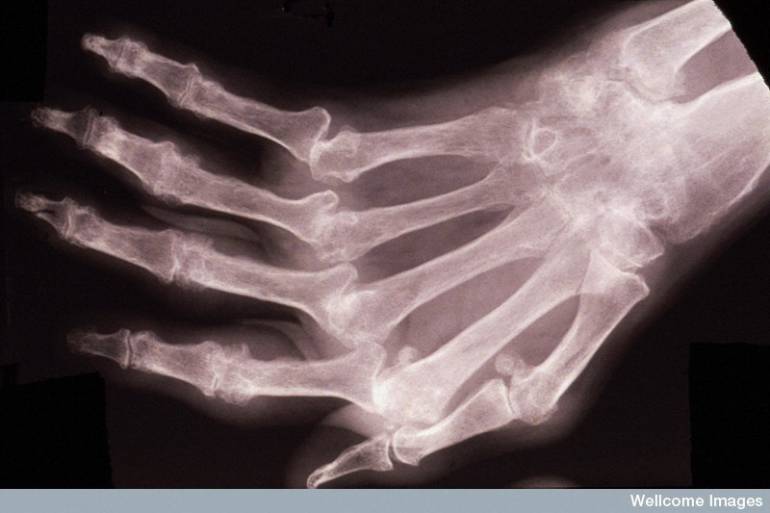

La AR es una enfermedad crónica, que además de la inflamación de las articulaciones, puede ocasionar problemas en órganos como los ojos, el pulmón, el corazón o el riñón. Algunos de sus síntomas más comunes son el malestar, cansancio, fiebre y limitaciones para trabajar o realizar actividades cotidianas.

“Sin una intervención a tiempo, la inflamación que produce la AR continuará aumentando y se presentará un daño irreversible en las articulaciones, llevando a deformidad y discapacidad. Además, la AR no es solo un problema articular, también puede comprometer diferentes sistemas, llevando incluso a una disminución en la expectativa de vida cuando no se realiza el tratamiento adecuado”, asegura el Dr. Toro.

Todas las personas son sensibles al desarrollo de la AR, aunque es más frecuente en las mujeres y se desarrolla normalmente entre los 30 y 50 años. Esta enfermedad es progresiva, puede comenzar de una forma leve y con el tiempo empeorar hasta causar daños y deformidades irreparables en las articulaciones afectadas.